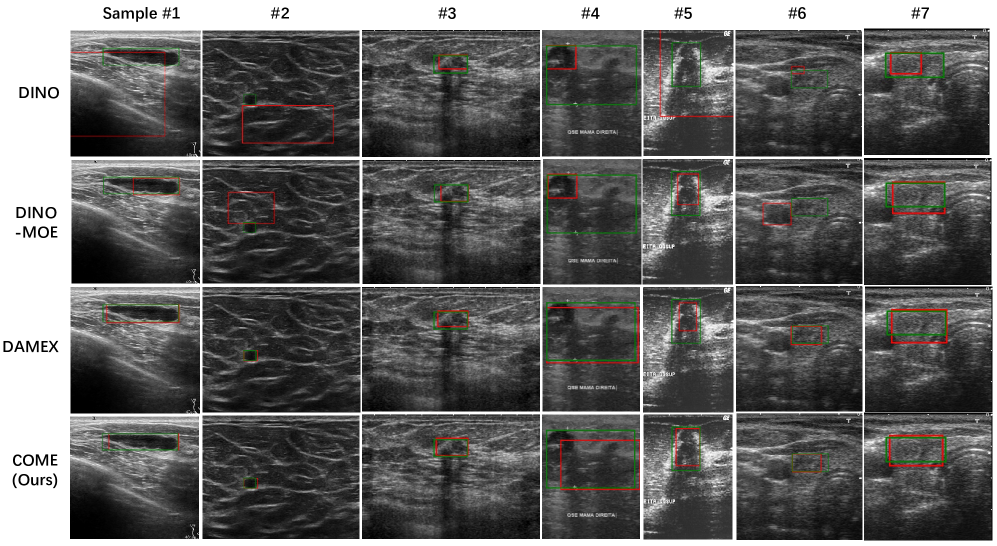

Refer to caption

Figure 3: We visualize lesion detection on the inter-organ integration benchmark, comparing the non-MoE model DINO, the MoE-based DINO-MoE and DAMEX, and ours. COME demonstrates strong performance across all heterogeneous datasets.

Tab. 2 compares COME with baselines across three training configurations: single-dataset (top), intra-organ (breast/thyroid) combinations (middle), and inter-organ integration (bottom), revealing key findings: 1) DINO (top section) achieves performance with -3.49% and -4.62% mean AP decrease over middle/bottom configurations respectively. Besides, the high computational cost of single-dataset training outweighs its performance gains, with poor generalizability causing significant performance drops on unseen data. 2) COME with Multi-Step clustering achieves the highest mean AP (5.14-7.42% improvement over baselines), demonstrating consistent gains across datasets through multi-source integration and cross-dataset correlation mining. 3) The 1.13% performance gain between bottom/middle tiers highlights enhanced inter-organ synergy and clinical viability. Notably, our framework achieves 9.79% (BUSI) and 15.59% (BUV) superiority over DINO, confirming its viability as a single-source training alternative. Further, We present visualization results of four models trained on the integrated intra-organ benchmark, highlighting image differences and showcasing the superiority of our COME, as shown in the Fig. 3.